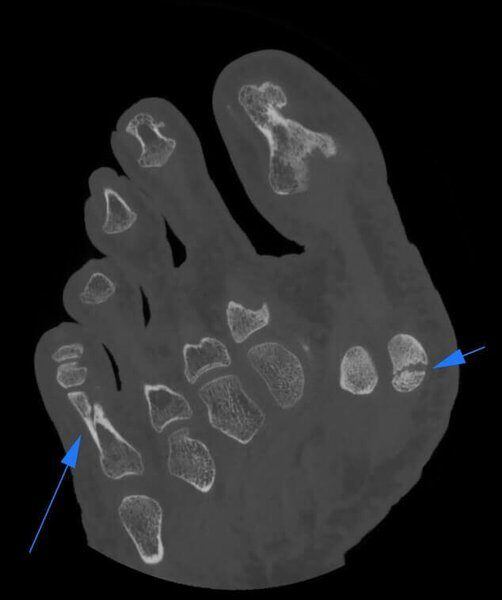

Frattura di osso Sesamoide e Falange